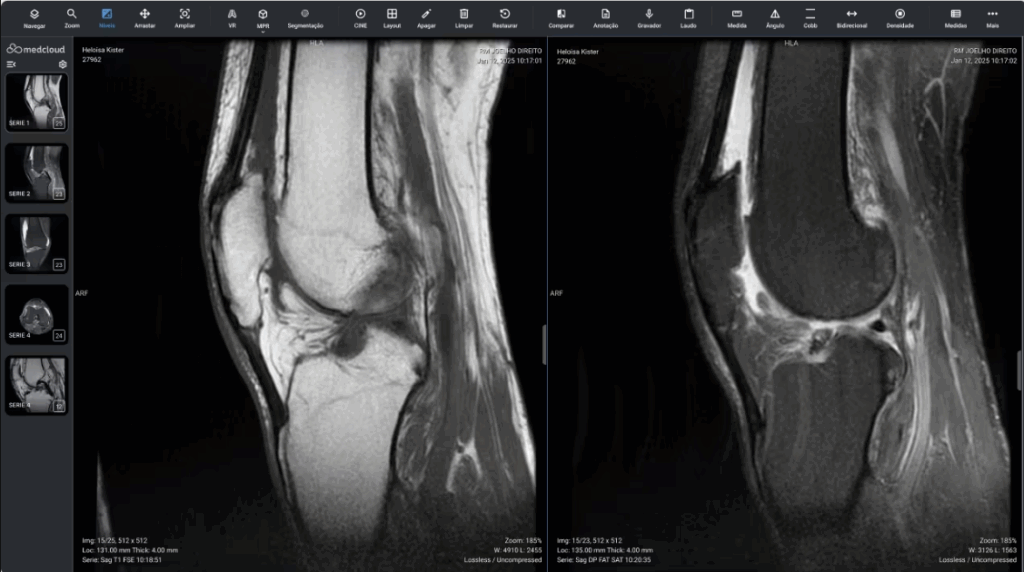

Herramientas con baja curva de aprendizaje. Su equipo se entrenó eficientemente en poco tiempo.

Con sólo unos clics y desde cualquier lugar. Trabajo de calidad y seguro en cualquier navegador de Internet.

Accede a los exámenes desde tu computadora de escritorio o usando tu computadora portátil dondequiera que estés. Acceda a informes, archivos adjuntos e imágenes en calidad original, además de todas las herramientas que necesita, dondequiera que vaya.

Calidad diagnóstica en cualquier lugar, en cualquier momento y en el menor tiempo posible.